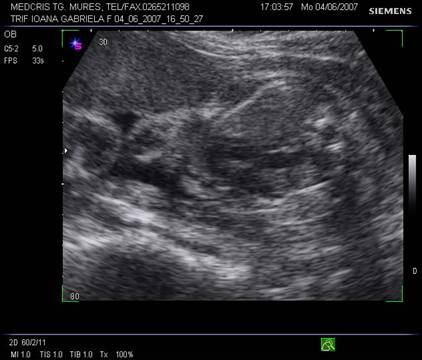

Fig. nr. 268. Formatiune anecogena abdominala fetala independenta de rinichi, la 28 sapt,ulterior in crestere la copilul de 3 ani

Fig. nr. 269. La peste 3 ani de la diagnosticul intrauterin, formatiunea tumorala abdominala ajunge la dimensiunea de 12 cm diametru si cu o structura inomogena cu mici hiperecogenitati sugestive ptr un teratom